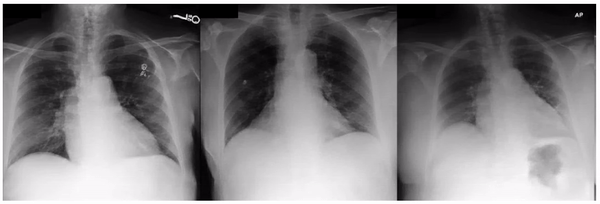

Positive controls

First, to ensure the framework successfully identifies known visual attributes, we examined tasks for each imaging modality, where some known attributes exist (i.e., “positive control” experiments). Indeed, we found that cortical cataract spokes were seen for cataract prediction from external eye photos, retinal vein dilation for smoking status prediction from fundus photos, and left ventricular enlargement for abnormality prediction from CXRs.

StylEx-0-Hero

Examples of “known” (positive control) attributes extracted by our approach: a) Spokes for cataract presence, which appear as radial opacities like spokes of a wheel; b) retinal vein dilation for smoking status; c) left ventricular enlargement for abnormal CXR.